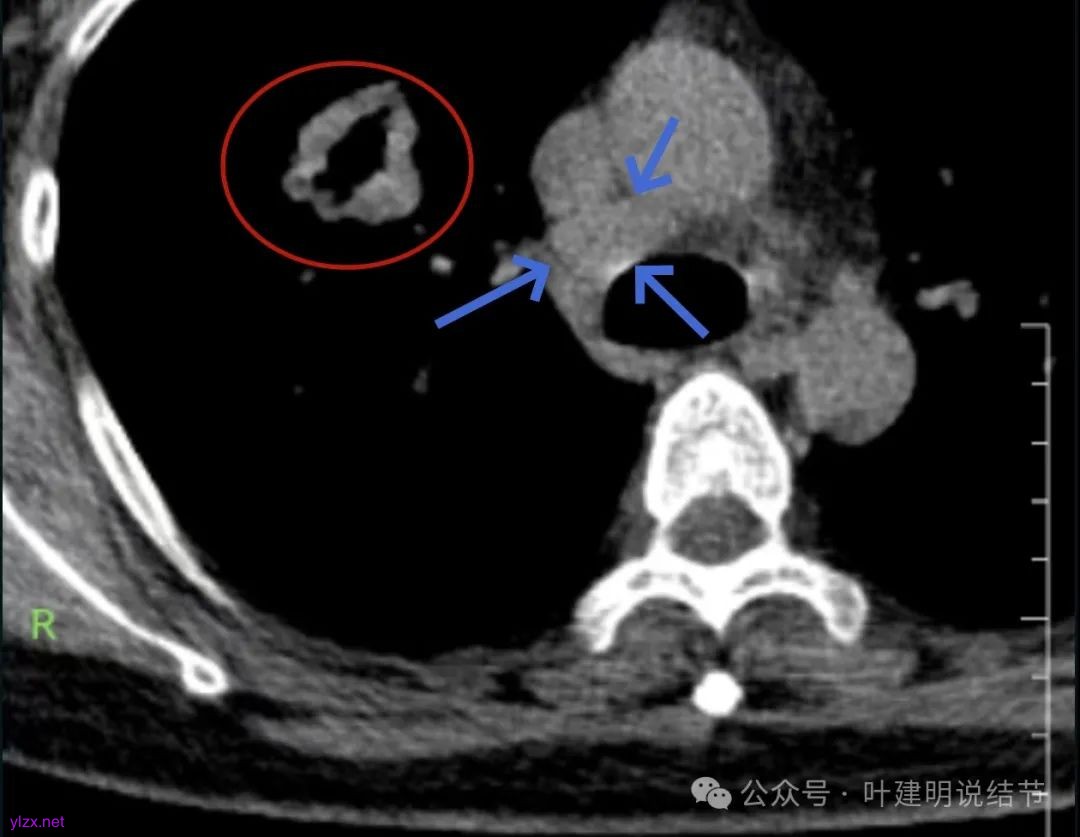

腔静脉旁明显肿大淋巴结。

你的右上叶这个病灶基本上肯定是肺癌,要尽快处理。从影像上看有以下特点:1、整体轮廓清楚,不似普通炎症的周围有晕或阻塞性改变;2、边缘明显的浅分叶,总体上的感觉膨胀性明显,不管哪个层面看上去都是鼓鼓的;3、边缘区域有磨玻璃成分而且也是分叶状的;4、部分层面见血管进入;5、空腔病灶的壁厚薄不均,内壁不光滑。我考虑中低分化肺癌,由于腔静脉旁有明显肿大淋巴结,需要进一步完善增强CT以及PET-CT检查以明确有无远处转移,是否仍可手术治疗(从病灶本身来说是可以肺叶切除治疗的)。要尽快处理。意见供参考!